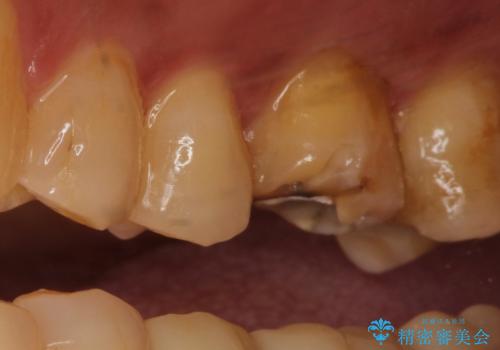

根管治療を行ったのち、症状改善を認めオールセラミッククラウンにて修復治療を行いました。

根管治療にはラバーダムシートをつけて行うことが大切です。マイクロスコープを使用し治療を行いました。治療後、歯の痛みは消失し、とても満足していただきました。

根管治療を行った歯は、再発防止や残された歯質を守るため、クラウンによる補綴治療が必要となります。